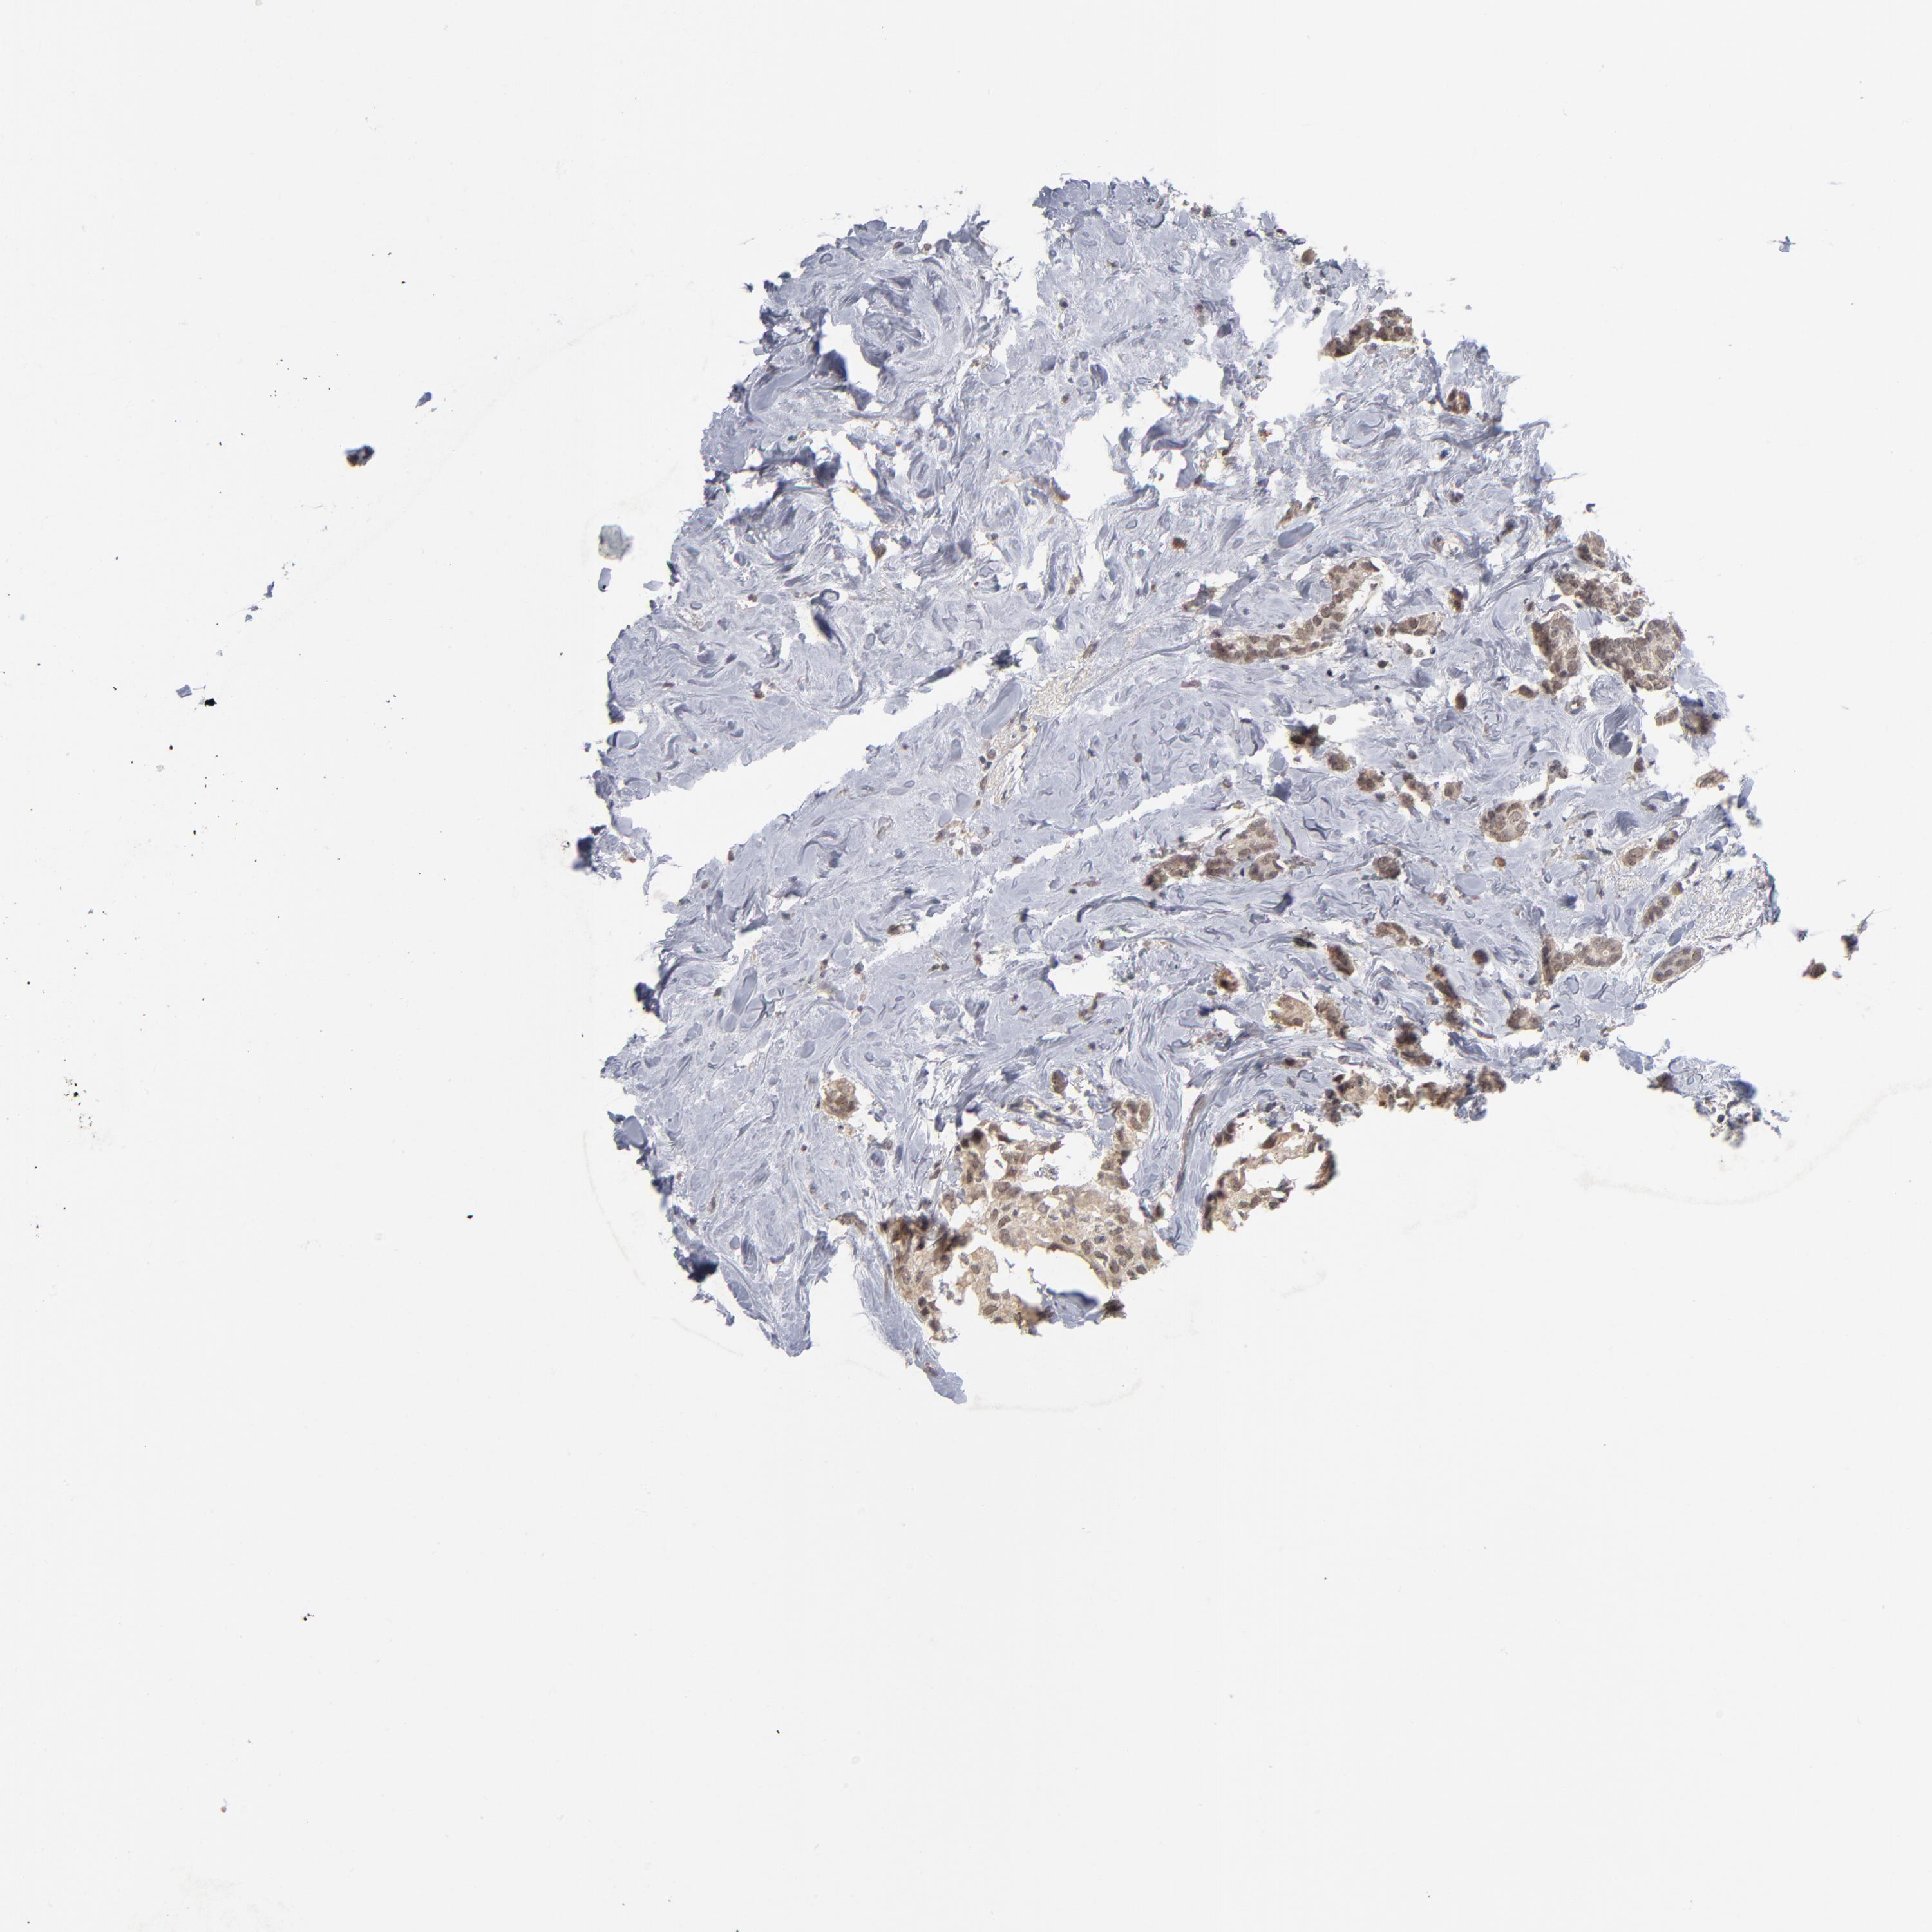

BRCA TCGA BRCA VALIDATION PROTEIN EXPRESSION

ANTIBODIES

AND

VALIDATION